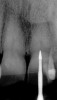

Figure 21   Preoperative condition with normal calcification of tooth No. 8 and advanced calcific degeneration of the pulp of tooth No. 9.

Figure 21